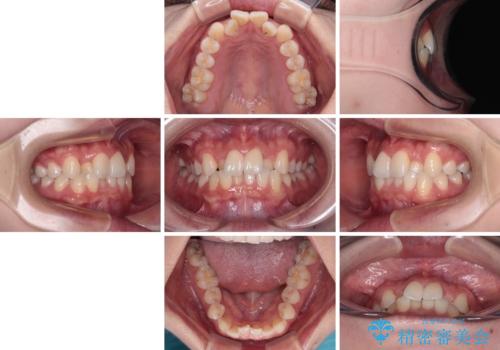

前歯のクロスバイト 裏側に隠れた歯をワイヤー装置で短期間治療

- 上顎前歯のクロスバイトを気にして来院された患者様です。

ワイヤー矯正でもマウスピース矯正でも対応可能でしたが、マウスピースによる自己管理に一切の自信がないとのことで、ワイヤー装置にて矯正治療を行うこととしました。